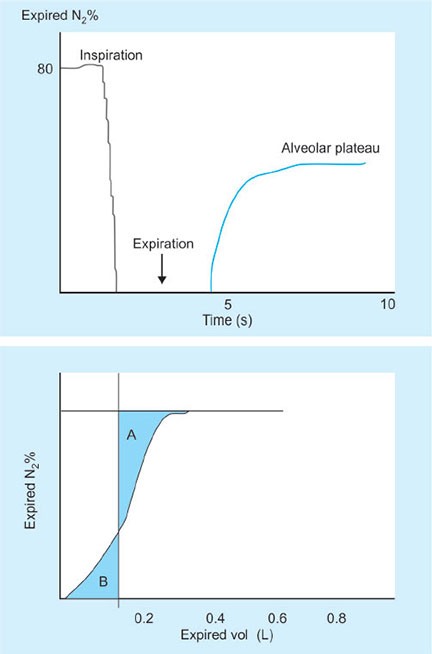

Measurement of Dead Space

- Fowler's method—tracer washout (Fig. 22)

- Single breath analysis using an indicator gas (N2, CO2, O2, He) to mark the transition between dead space and alveolar gas

- The mid-point of the wash-in (where area A = area B below) measures the transition from conducting airways to the transition from dead space to alveolar gas

- In patients with nonuniform distribution of ventilation, i.e. regions of the lung with different time constants, a slow “wash-in” is seen and the method is inaccurate.